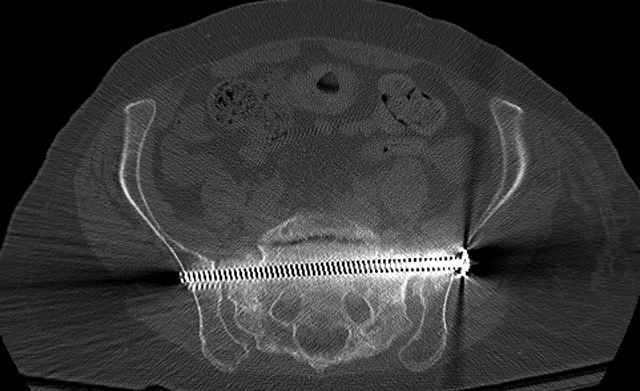

Pelvic CT Scan - 3 Months After Fall

Sacral Injuries

Ramus Fractures